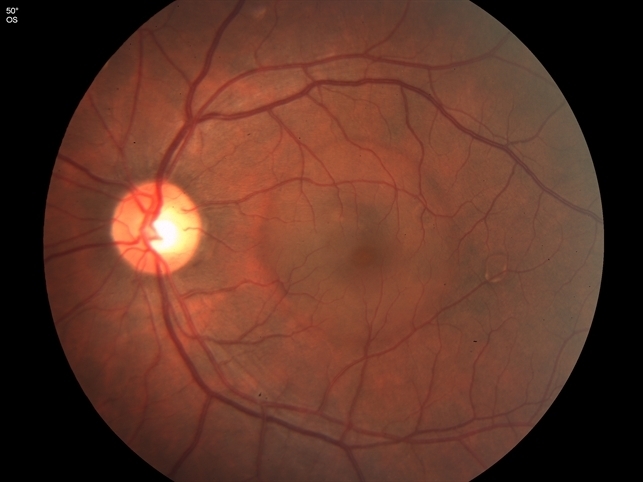

На глазном дне определяется пузырь серозной отслойки нейросенсорной сетчатки, расположенный в области макулы, имеющий четкие границы и обычно округлую форму. Его диаметр составляет 1-3 диаметра диска зрительного нерва. Помимо отслойки нейроэпителия часто выявляются дефекты пигментного слоя, отложения субретинального фибрина, липофусцина. Субретинальная жидкость прозрачна, нейросенсорная сетчатка не утолщена.Эта отслойка гораздо проще выявляется при офтальмоскопии с бескрасным фильтром, а ее границы четче видны (иногда буквально «вспыхивают») при офтальмоскопии с максимально диафрагмированным источником света. Объясняется такое свечение границ отслойки тем, что при незначительной глубине серозной полости свет проходит по ней, как по светопроводу, выходя в стекловидное тело на границе прилежащей сетчатки.